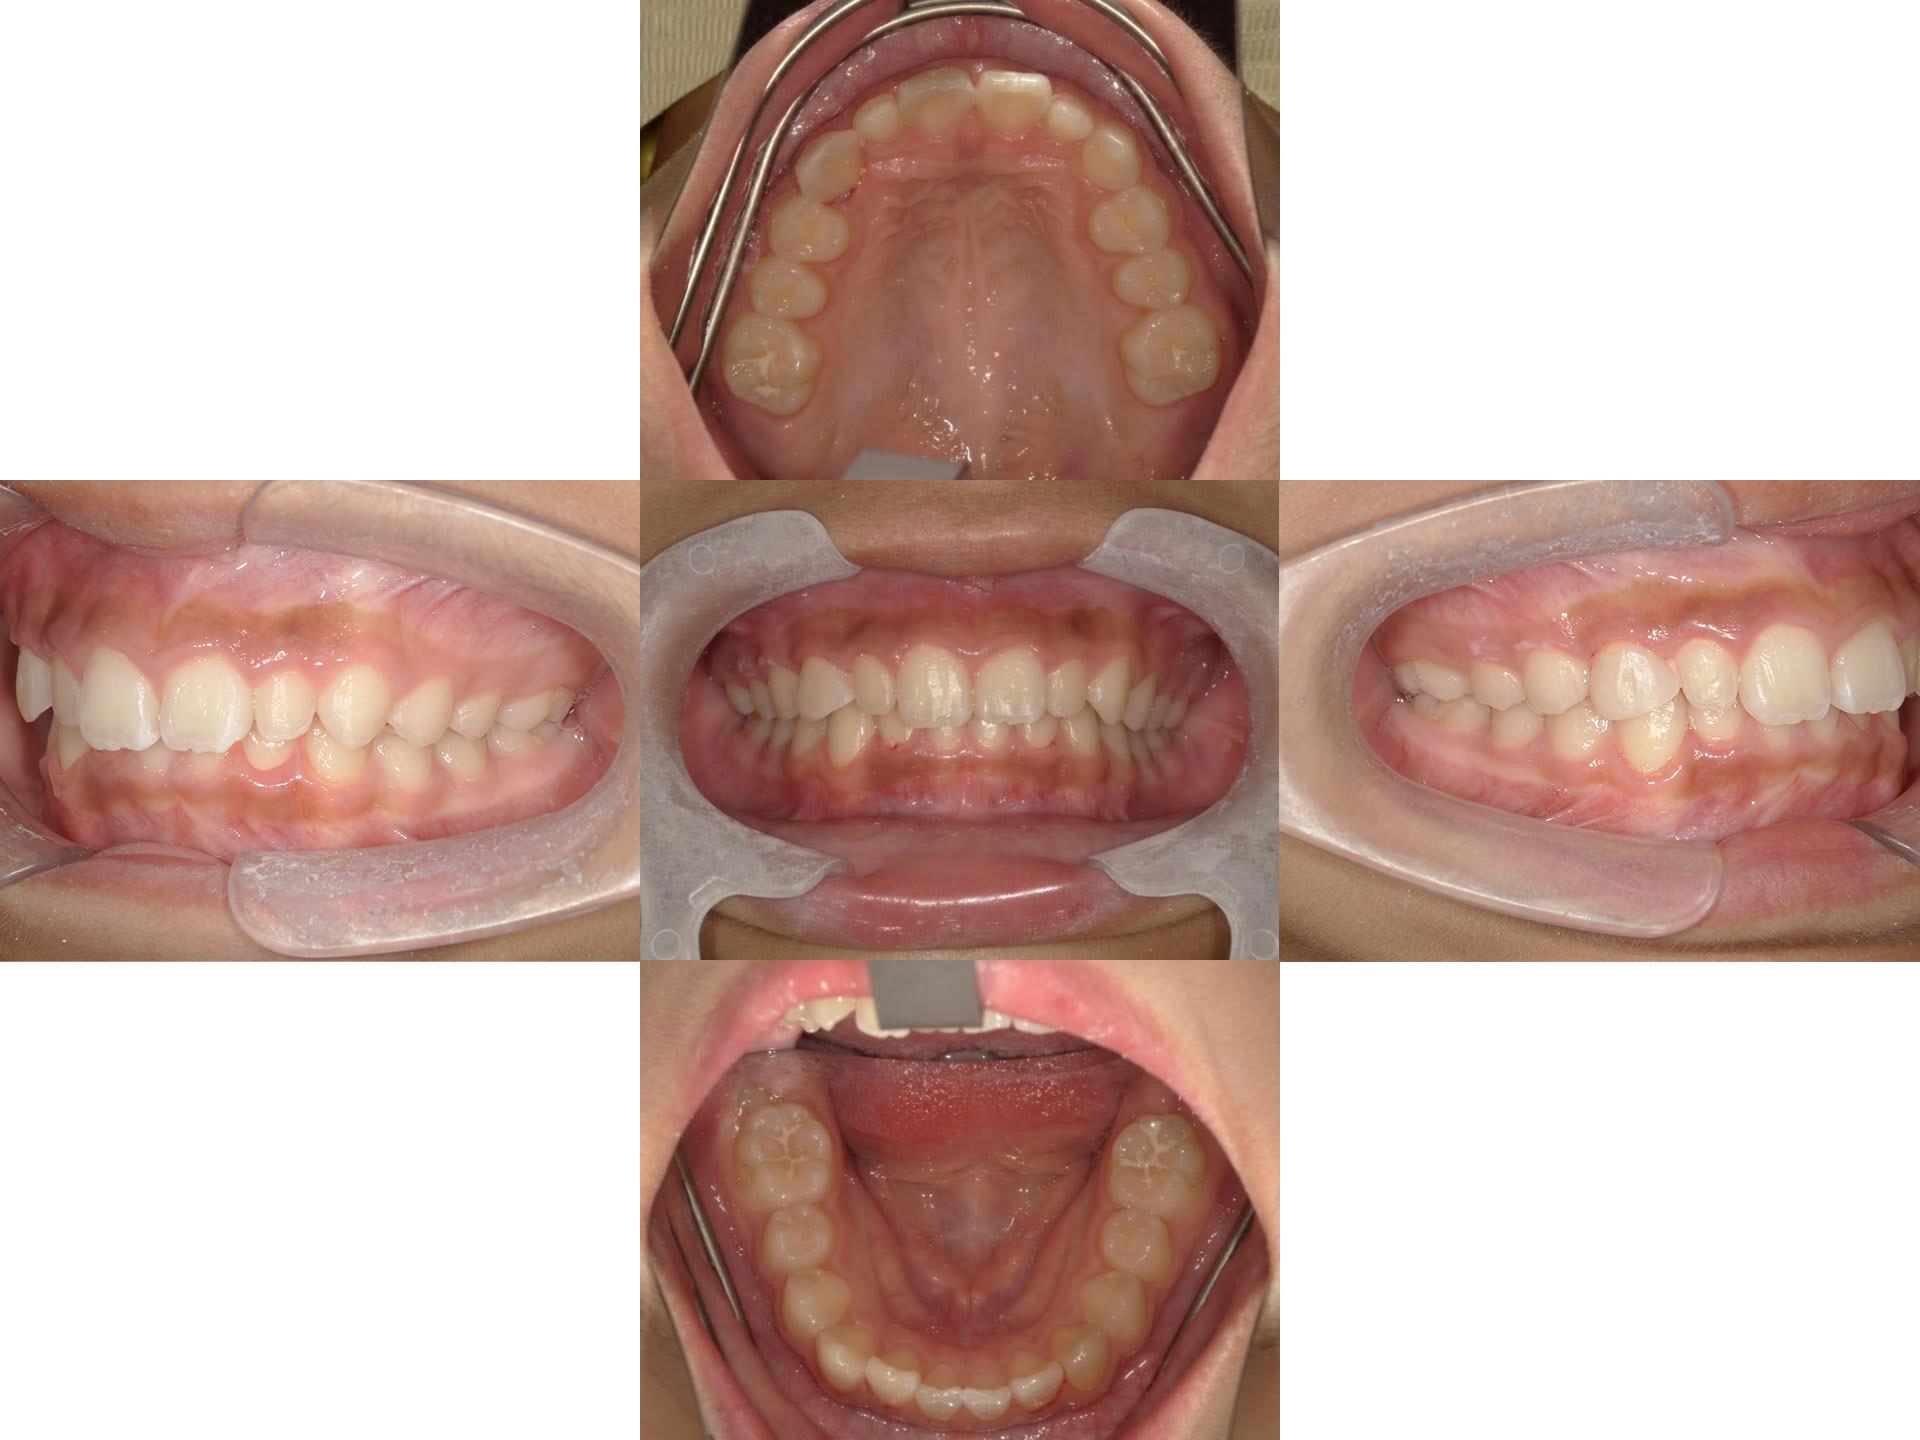

治療前

| 患者様 | 10代(小学生)女性 |

|---|---|

| 主訴 | 歯並びの乱れを改善したい |

| 治療内容 | マウスピース矯正(非抜歯) 矮小歯の右上3番にコンポジットレジンを貼り付ける治療を実施 |

| 治療期間 | 1年9ヶ月 |

| 通院回数 | 26回 |

| 治療費 | 小児矯正診断料 3万3千円(税込) マウスピース矯正 44万円(税込) 毎月の管理・処置料金 4400円×20回=88000円(税込) 合計64万9000円 |

| リスク | 矯正のマウスピースによる不快感や痛みがある場合があります 歯の動きには個人差があり、当初予定されていた治療期間より時間がかかる場合があります |